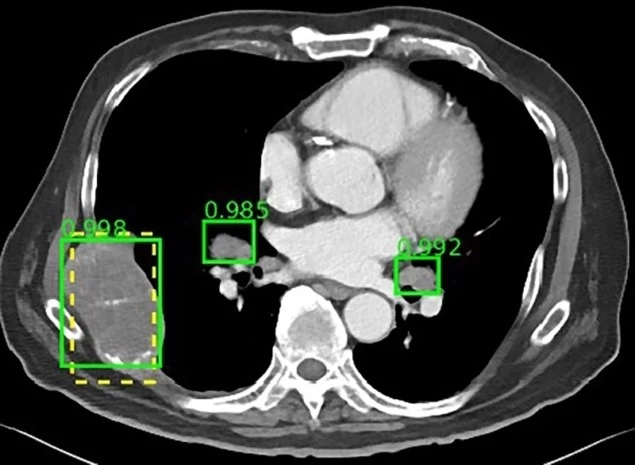

DeepLesion通过提供足够强大的CT扫描数据库和附带的标注来训练深度神经网络,从而帮助绕过这些障碍。美国国立卫生研究院建议,有朝一日可以“使科学界能够创建一个具有统一框架的大规模通用病变检测器”。

该数据库包括来自马里兰州贝塞斯达NIH临床中心的4400多名患者的大约10600项研究。虽然目前大多数数据库包含10至数百个单一类型的病变,但该组设计的DeepLesion可容纳超过32000个病灶,涵盖各种放射学发现,如肺结节、淋巴结肿大和肝肿瘤。

有了多范畴的病变数据库,DeepLesion为研究人员提供了开发人工智能算法的机会,能够自动检测和诊断多种病变类型。美国国立卫生研究院指出,未来它还可能发展成为一个通用病变检测器,可用作初始筛选工具,并将其结果发送到其他更专业的算法。此外,研究人员可能可以在同一次CT扫描中研究不同类型病变之间的关系,从而全面评估癌症负担。

为了开始展示这种潜力,Summers及其同事用DeepLesion数据库来训练一个典型的通用病变检测器,以发现各种病变。他们的探测器灵敏度达到81.1%,每个图像有5个假阳性。